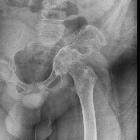

- pelvis

Plain radiograph and CT

- intramedullary or subcortical lucent foci may be the earliest manifestation

- this progresses to profound osteolysis with resorption of affected bone and lack of compensatory osteoblastic activity or periosteal reaction